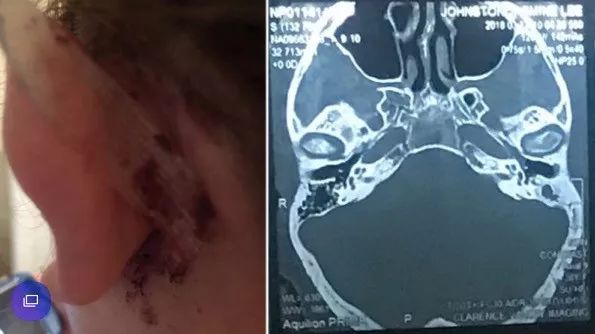

随着时间推移,感染已蔓延至大脑,从而引发了癫痫。医学团队的CT扫描显示:他的头骨下靠近左耳道的位置有两块充满脓液的肿块,再晚治疗情况就危险了。

为有效消除感染,医生进一步寻找着致病的根源。终于在脑成像的帮助下他们发现男子的耳道中有一个异物。经过鉴定,导致严重感染的东西是一小撮棉花。